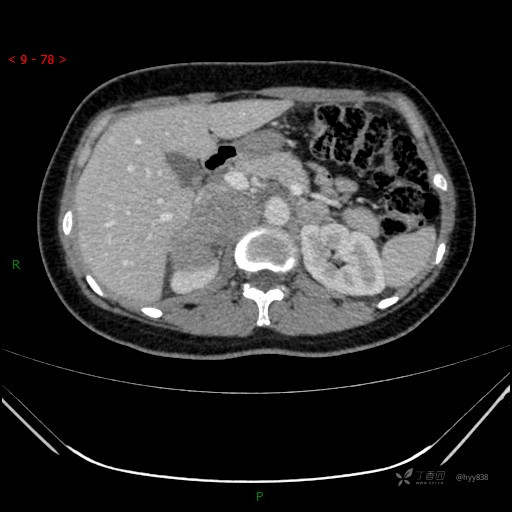

辅助检查:CT

动脉期